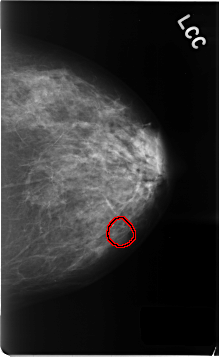

C_0468_1.LEFT_CC

LEFT_CC LINES 4632 PIXELS_PER_LINE 2840 BITS_PER_PIXEL 12 RESOLUTION 50 OVERLAY

FILE: C_0468_1.LEFT_CC.OVERLAY

TOTAL_ABNORMALITIES 1

ABNORMALITY 1

LESION_TYPE MASS SHAPE OVAL MARGINS OBSCURED

ASSESSMENT 3

SUBTLETY 2

PATHOLOGY BENIGN_WITHOUT_CALLBACK

TOTAL_OUTLINES 1

BOUNDARY